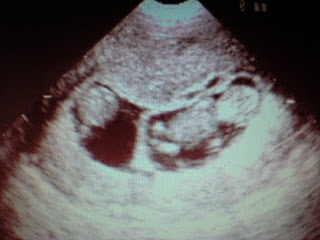

· ULTRAHANGOS VIZSGÁLAT IKERTERHESSÉGNÉL